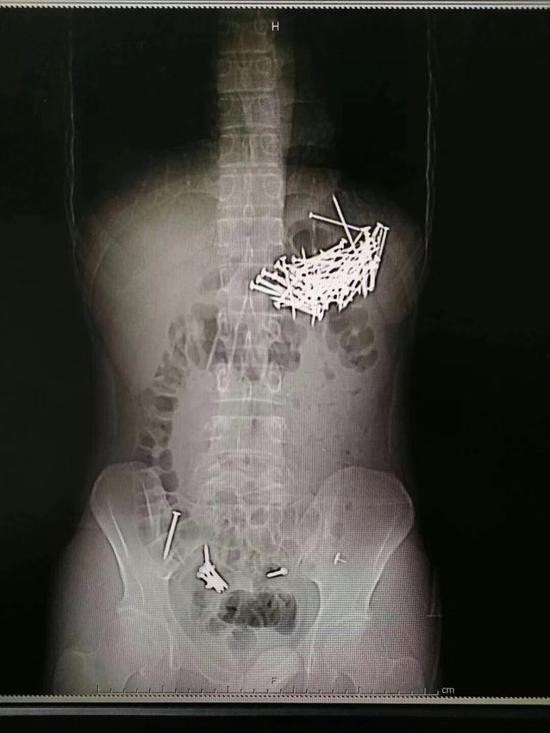

小伙子体内被发现大量钉子 医院供图

8月8日晚上,湖南省郴州市第一人民医院接到求救信息,一个在北湖路某酒店居住的小伙子称自己吃了包子后肚子疼痛难忍,需要医生急救。120急救人员将其接到医院后发现,小伙子所吃的包子馅有异常。“拍片之后可以看到,他的肚子内有大量钉子状物体。”郴州市第一人民医院一名值班医护人员表示,在手术之前,小伙子交给医生一封写给女友的“遗书”,说是若找不到亲属,可以打电话给女友。

8月9日晚上7时许,联系到小伙子的亲属之后,医院制定了手术方案并取得家属同意,经过4个小时的忙碌,医生从小伙子的腹腔和胃部等取出共87根铁钉,每根钉子大约四五厘米长。“见过吞食异物的病人,但是没有见过吞下这么多钉子的病人。”一名医护人员表示,小伙子自称是吃了“钉子馅”包子,“肯定是一时想不开,才做了傻事,这可忙坏了我们连夜做手术的医生,醒来之后我们得好好劝劝他。”

据手术医生胡志辉介绍,经过检查和手术证实,这个小伙子吞食了87根铁钉和7枚图钉,其中6枚图钉被病人自行排出,目前余下一枚图钉在直肠附近,由于体积较小,病人应该可以自行排出。